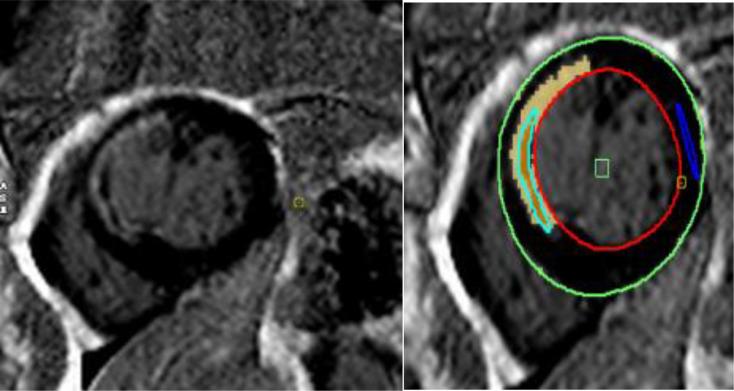

We prospectively enrolled a cohort of 78 patients who presented with new-onset ST-segment elevation myocardial infarction and who underwent successful emergent PCI within 12 h from the onset of symptoms. Late gadolinium-enhanced LGE (LGE) was quantified via CE-CMR, and patients were categorized into two groups on the basis of the median LGE value.

我们前瞻性纳入了一组78例首次发生ST段抬高型心肌梗死且在症状发作后12小时内成功进行急诊PCI的患者。通过CE-CMR对延迟钆增强(LGE)进行定量分析,并根据LGE值的中位数将患者分为两组。